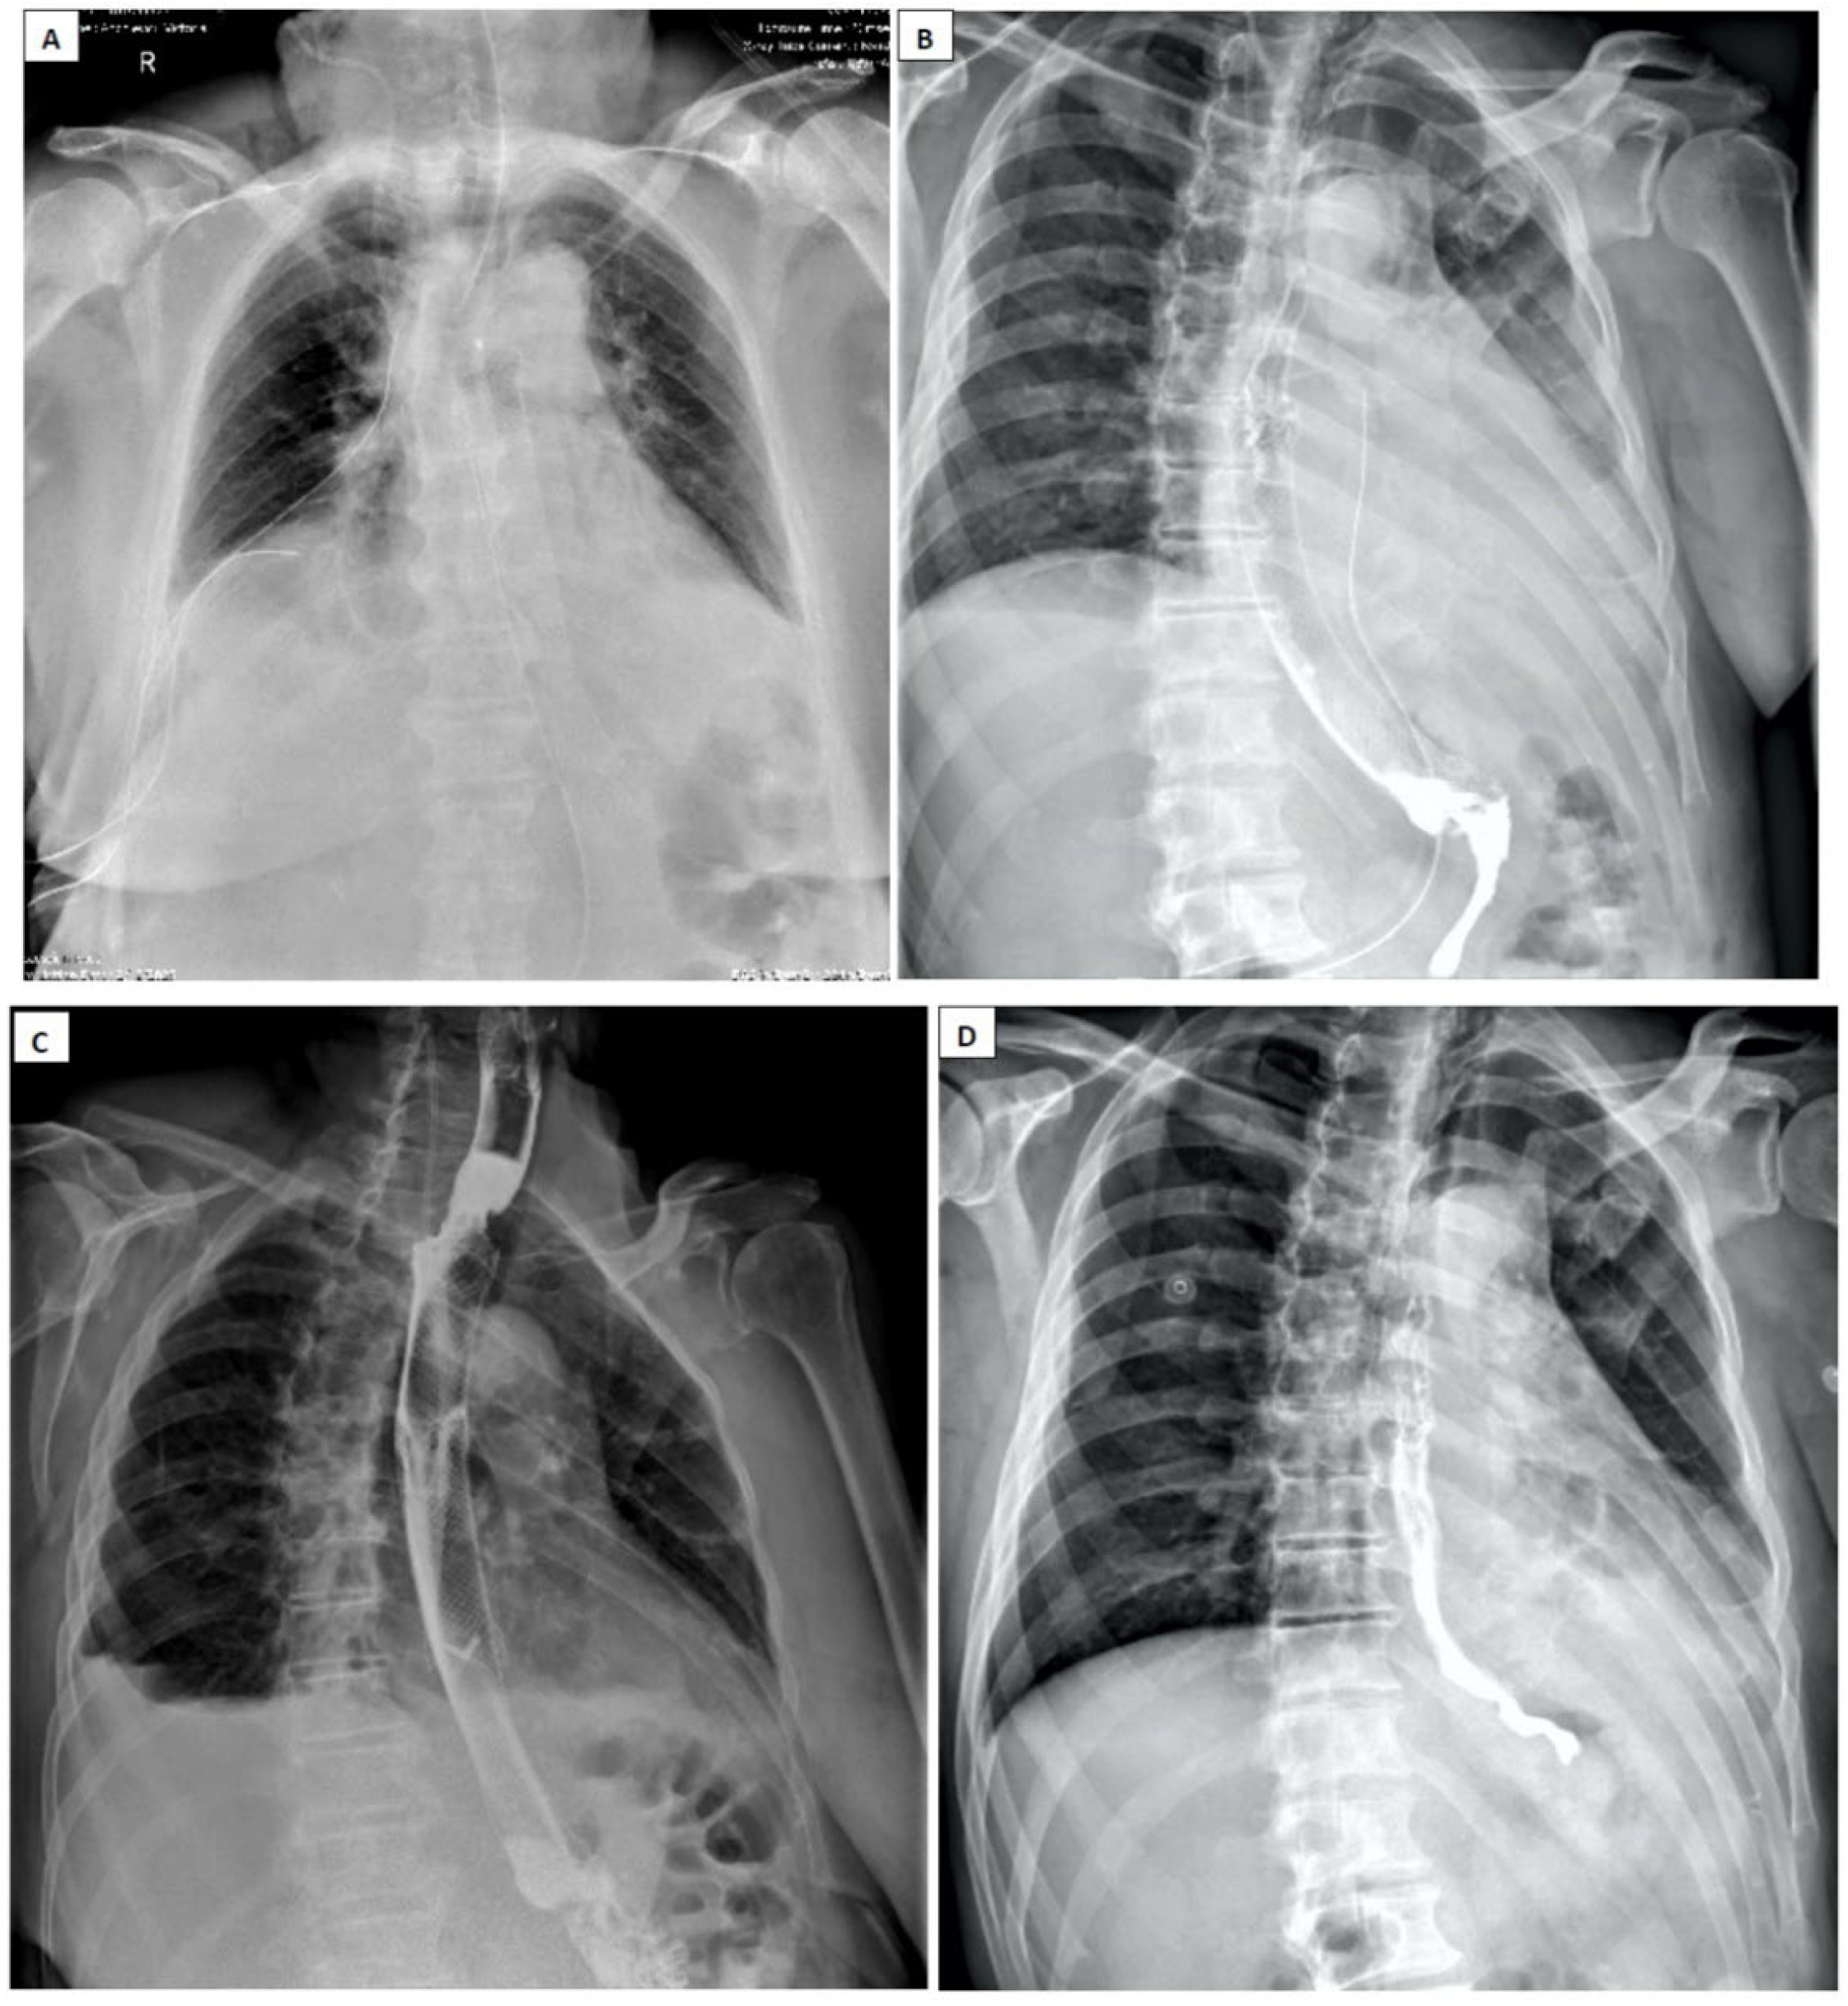

- Pneumomediastinum

- Pneumothorax (especially left-sided)

- Pleural effusion (especially left-sided)